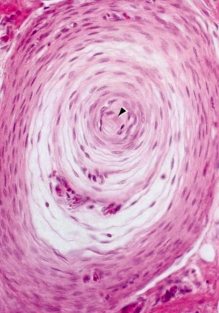

Pacinian Corpuscle - deep in integumen, deep vibration sensation